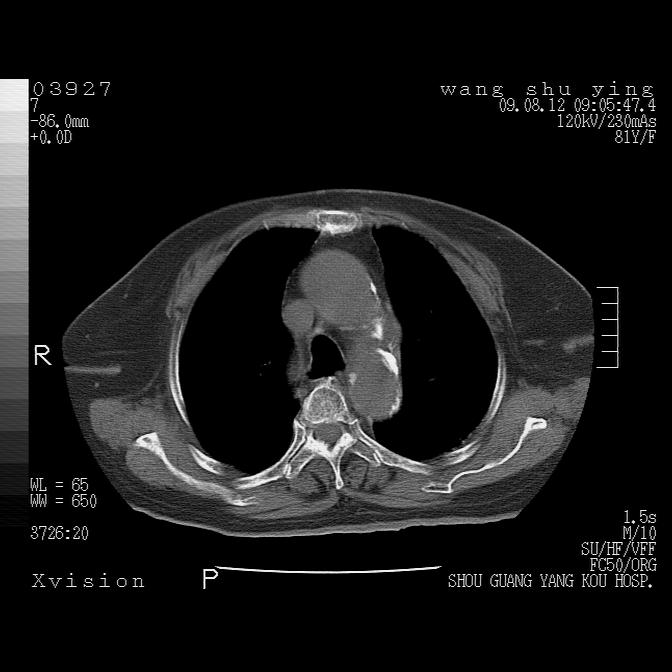

以下是引用帅河马在2009-8-12 12:59:00的发言:[br]两肺感染性病变伴双侧胸膜肥厚。[br]左侧甲状腺腺瘤不除外。[br]腹水+心包积液。[br][br][本贴已被 帅河马 于 2009-8-12 13:14:32 修改过]

以下是引用sdzyy在2009-8-12 18:17:00的发言:[br]两肺感染性病变伴双侧胸膜肥厚。[br]左侧甲状腺腺瘤不除外。[br]腹水+心包积液。[br]支持

以下是引用随光逐影在2009-8-12 19:42:00的发言:[br]1)两肺感染性病变伴双侧胸膜肥厚。2)不排除左侧甲状腺腺瘤。3)肝脏占位性病变;建议行进一步检查。